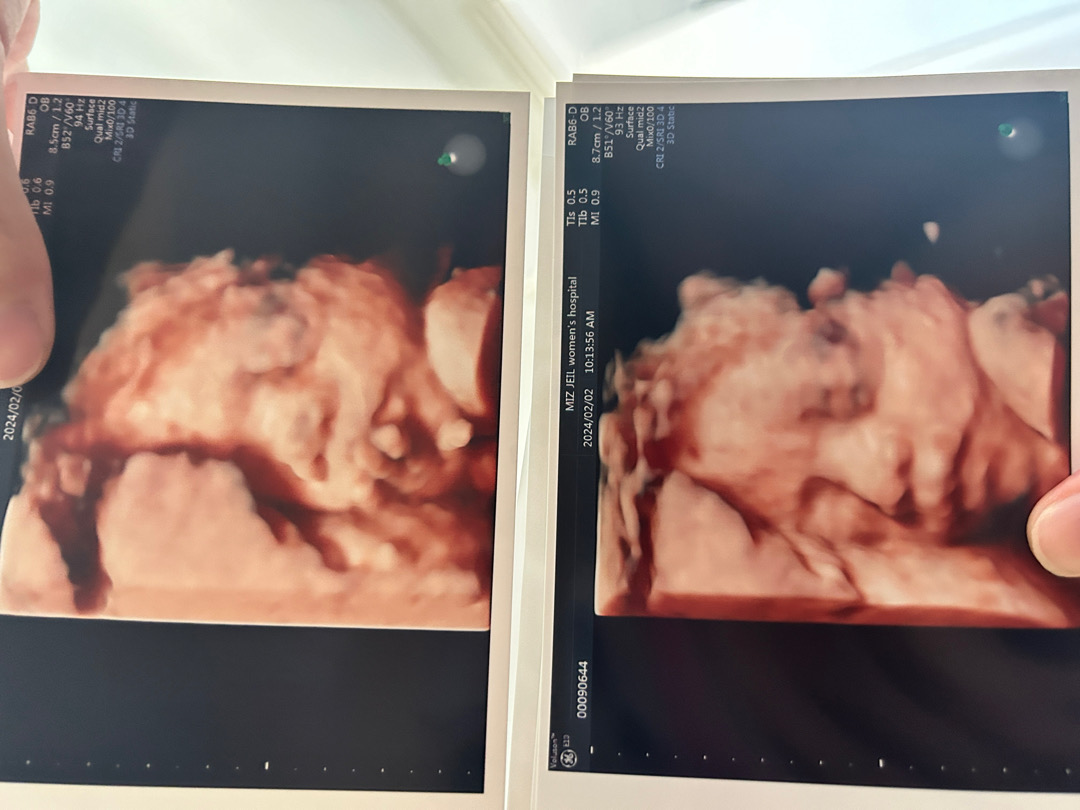

입체초음파... 제 지분이 없네용ㅠㅋㅋㅋ

첫 아이에요🤭 남편은 인생의 목표가 딸바보였다는데, 딸이라는걸 알고 울었어요ㅋㅋㅋㅋ 얼마전에 입체초음파를 했는데 너무 남편인거에요?ㅎㅎㅎ 진짜.... 제가 ‘자궁만 빌려준거 같아...’라고 했더니... 그런 무서운 말 하지말라며 지금 몇날며칠째 입이 찢어져요....ㅋㅋㅋ 그게 웃기면서 저도 좀 닮았으면 좋겠는데... 딸인데... 아빠닮아서 얼굴 크면 안되는데... 그건 아빠가 억대 연봉을 받아도 해결안되는데... 문득 걱정이네요ㅋㅋㅋㅋ